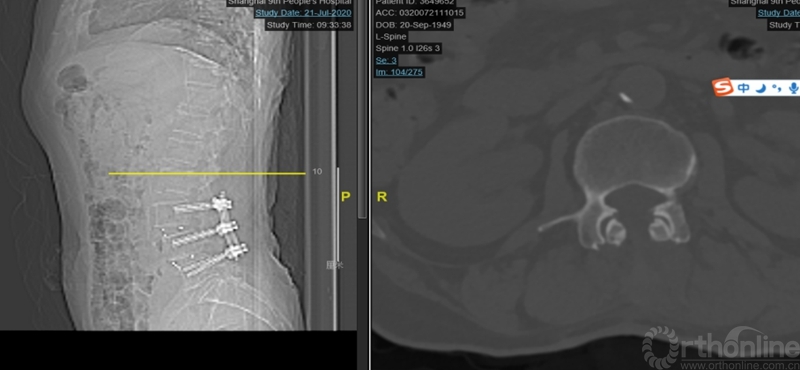

观察24小时后无明显改善,再次行开放腰椎全椎板扩大减压术,近端矢状面扩大减压延伸过腰椎矢状面顶椎(图8),左侧腰4、5及骶1神经根管扩大减压,直至肉眼辨别无明显交界区卡压和神经根紧张(图9)。

图8:第二次减压近端延伸至腰2椎体后方,保留腰1-2小关节完整

图9:第二次减压腰2至腰5全椎板减压,腰2-3小关节保留